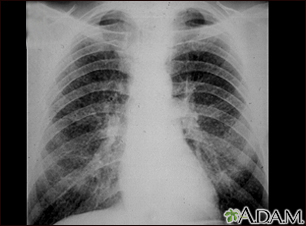

Coal workers pneumoconiosis - stage IIBackCoal workers pneumoconiosis - stage IIThis chest x-ray shows stage II coal worker's pneumoconiosis (CWP). There are diffuse, small light areas on both sides of the lungs. Other diseases that may explain these x-ray findings include simple silicosis, disseminated tuberculosis, metastatic lung cancer, and other diffuse, infiltrative pulmonary diseases. E-mail FormEmail ResultsName:Email address:Recipients Name:Recipients address:Message: